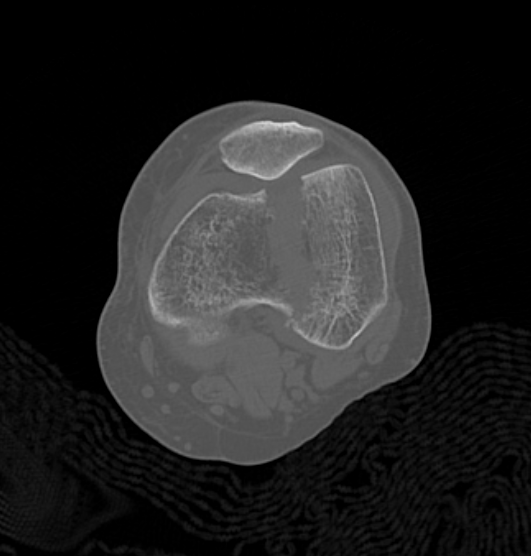

Type C: Complete articular

Xray / CT